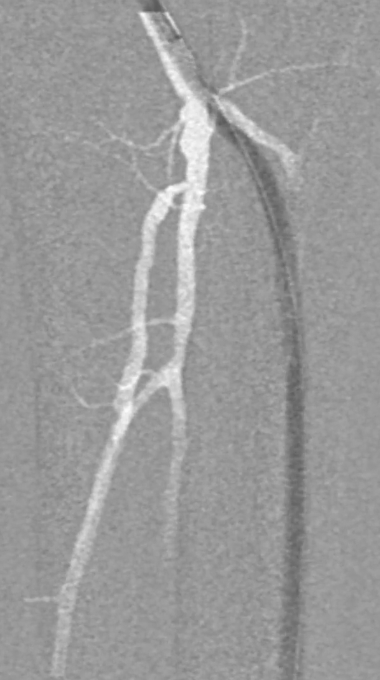

栓塞处理:造影发现管腔获得尚可,但是流速明显较慢,考虑保护伞上方管腔闭塞(考虑斑块/血栓脱落),用6F导管反复抽吸后收回保护伞。

夹层发现及处理:

更换V18导丝后造影显示,胫后动脉血流通畅,胫前动脉疑似仍有小的血栓脱落,导致栓塞。

股浅动脉全程管腔获得尚可,但中段有明显的夹层形成,

先用5mm长球囊充分预扩张;再次造影显示,股浅动脉近中段管腔获得良好,中远段仍有大量的夹层

采用药物涂层球囊(DCB)对股浅动脉病变段全程覆盖:近端用5-250新型药涂球囊,远端用5-150 impact 药涂球囊;

造影显示中段仍有局限性夹层,为保证远期通畅率,植入补救性支架并以5mm球囊后扩张